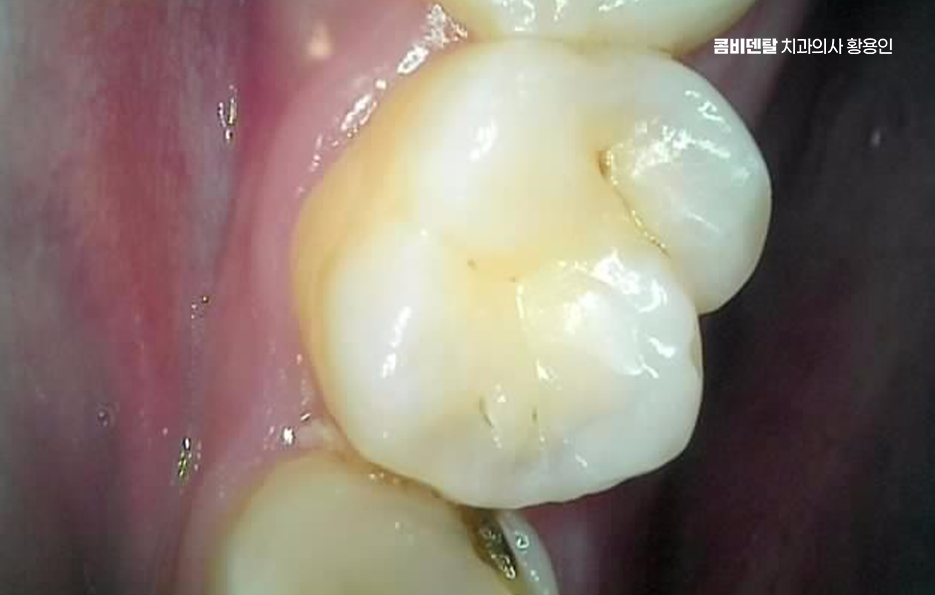

출처 아카이브 열기얼마 전부터 오른쪽 아래 어금니 근처가 묘하게 불편했어요, 처음에는 그냥 음식물이 좀 더 자주 끼는 것 같다고만 생각했는데, 어느 날부터 양치할 때 그쪽을 닦으면 묘하게 시큰한 느낌이 들었어요, 아프다고 할 정도는 아닌데 묘하게 예민하고, 시린 듯도 하고, 찜찜한 기분이 남아서 괜히 그쪽은 피해서 양치하게 되고, 그러다 보니까 오히려 더 불결하게 관리된 게 아닐까 싶은 걱정도 들기 시작했어요, 그렇게 결국 알게 된 사실은 사랑니에 충치가 생겼고, 그 사랑니 바로 앞에 있는 어금니까지 영향을 받아 충치가 함께 진행되었어요. 결국 이렇게 문제가 생기고 나니까 진작 사랑니를 뽑을 걸 하는 후회가 한꺼번에 밀려왔어요 왜 하필 그 끝에 있는 사랑니 때문에 앞에 있는 어금니까지 같이 망가졌을까, 그 어금니는 평생 써야 하는데, 이미 위치 자체가 안 좋은 사랑니 때문에 멀쩡한 어금니까지 문제가 되었다는게 안타까웠어요

다시 말해 사랑니가 문제를 일으키는 건 워낙 흔한 일이지만 사랑니 하나만 문제를 일으키는 게 아니라, 그 옆 어금니까지 같이 충치가 생기는 경우도 생각보다 많은데 특히 아래쪽 사랑니가 옆으로 누워 있는 경우에는 그 앞 어금니와 밀착돼 있어서 둘 사이가 잘 닦이지 않고 음식물이 잘 끼기 쉬운 구조라고 할 수 있었어요.

이런 사랑니는 앞 어금니와 비정상적인 접촉을 하게 되면서 음식물이 계속 끼고 세균이 쌓이게 되며 아무리 양치질을 잘한다고 해도 물리적으로 칫솔이 닿기 어려운 구조라서 결국 충치나 염증으로 이어지는 경우가 많은 거예요

문제는 여기서 끝나지 않고 누운 사랑니와 앞 어금니 사이에 충치가 동시에 생기는 경우는 치료가 더 복잡해질 수 밖에 없는데 왜냐면 사랑니가 옆으로 누워 있으니까 앞 어금니 뒷면에 생긴 충치를 제대로 보기도 어렵고, 치료 기구가 들어갈 공간도 부족해져서 충치 치료가 더 까다로워지는 것이며 특히 앞 어금니 뒷면에 생긴 충치는 환자도 자각하기 어렵고, 진단 시기도 늦어지는 경우가 많아서 이미 신경까지 손상됐거나 신경치료가 필요한 상태로 발견되는 일도 많이 있었어요